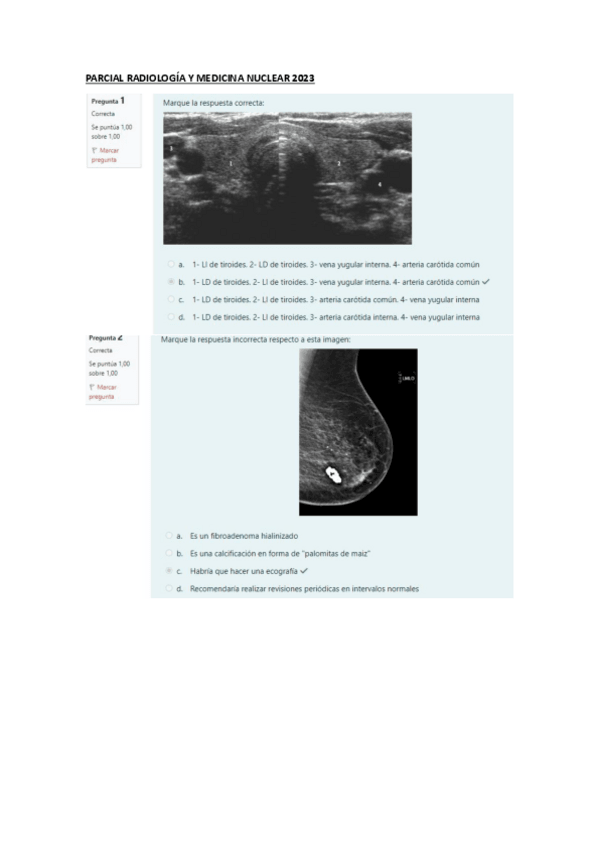

He publicado nuevos examenes de 3º radiología y medicina nuclear: PARCIAL-RADIOLOGIA-Y-MEDICINA-NUCLEAR-2023.pdf

5 páginas